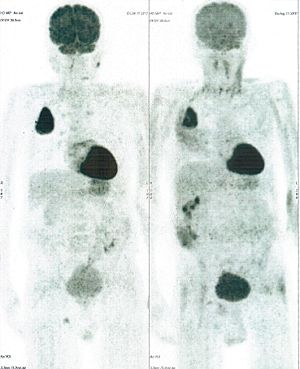

Below are some of the cases, from more than 80 cases we have treated so far with good results. When reading the PET/CT scans, the picture on the left is before treatment, and the picture on the right is after treatment. The intensity of black represents the activity of the cancer, but some black areas are not cancer: brain, heart, radioactive urine in bladder. For the heart, the intensity of black depends on the number of hours of fasting: if more than 10 hours, the heart is not even black, but if fasting is less than 6 hours, it is very black. The intensity of black in the brain can be variable in different scans depending on the brain activity at the time of the scan. The intensity of black in the radioactive urine can also be variable due to the hydration of patients and the time of injection of diuretic.

CASE NO: 1

(HEPATOCELLULAR CARCINOMA + STOMACH CANCER)

A middle-aged women who is very thin and very weak, can hardly walk, lying in bed most of the time. She saw a cancer specialist in a top hospital who discovered that she had massive hepatocellular carcinoma, and another cancer in the stomach. Given that hepatocellular carcinoma is incurable and stomach cancer is very difficult if not impossible to cure without surgery, she was told that nothing could be done for her. She came to ask us to help her. After just 4 treatment, the hepatocellular carcinoma went into remission, and the stomach cancer (arrow) became less active. Until today, more than 6 months later, the hepatocellular carcinoma is still in remission.

CASE NO: 1 - A FEW MONTHS LATER

A few months after successful treatment for hepatocellular carcinoma, and partially successful for stomach cancer, the PET/CT scan showed the stomach cancer becoming very active, with several metastases to the parts of the liver not previously involved by hepatocellular carcinoma. After a few treatment, all the active stomach cancer lesions in the stomach and in the liver went into remission.